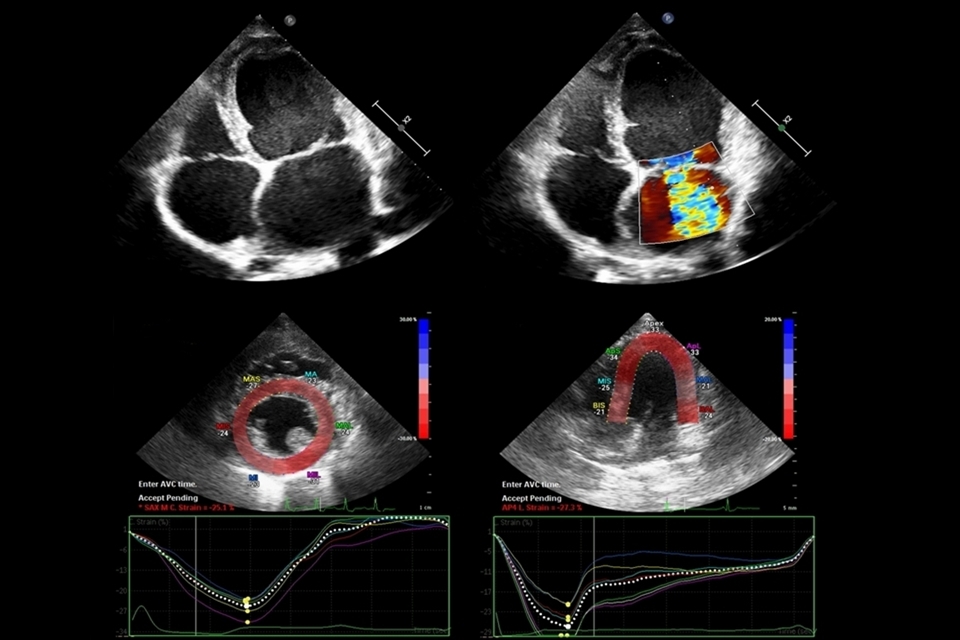

O exame ecocardiográfico de rotina inclui a avaliação subjetiva e as mensurações feitas a partir dos modos B, M e Doppler. O modo-B, também chamado ecocardiografia bidimensional, avalia o coração em planos compostos pela profundidade e largura. Nessa modalidade é possível visualizar alterações anatômicas ou defeitos congênitos. Já o modo-M fornece uma visão unidimensional do coração (apenas em plano de profundidade) em relação ao tempo, permitindo documentar as dimensões e o movimento do coração ao longo do ciclo cardíaco. Por fim, o método Doppler avalia a direção e a velocidade do fluxo sanguíneo, permitindo detectar fluxos anormais e turbulentos, calcular o débito cardíaco e demais parâmetros hemodinâmicos.